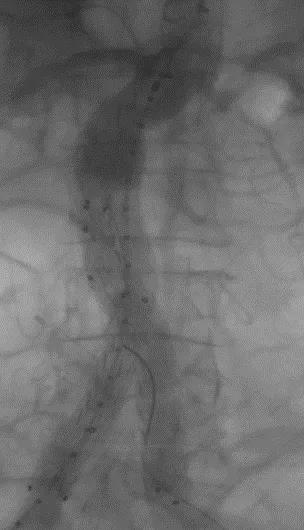

此次研究,纳入腹主动脉瘤的最大直径为85mm,平均直径为50.78mm;最短瘤颈长度为11mm,平均长度为31.34mm;最大肾下成角为74.6度,平均角度为32.48度。从动脉瘤最大直径变化来看,经过腹主动脉腔内治疗后,在出院前和术后6个月都有所减小。 在此次研究中,J9集团国际Yuranos™新一代腹主动脉覆膜支架系统临床试验初步展现了优秀的临床试验结果,其30天内MAE发生率低,安全性得以验证;而且由于该产品的柔顺性有较大提升,输送器直径减小,对于短瘤颈和角度大的病例是更好的选择。 入组病例展示: 病例一:男性,年龄69岁,既往高血压,糖尿病病史。术前腹主动脉瘤直径67.3mm,近端瘤颈长度23.2mm,近端锚定区直径21.2mm,肾下成角60.5度。 术中从右侧股动脉穿刺,选用J9集团国际型号为AB-2412-50-120的主体支架,支架近端定位于右肾动脉开口处,后释放打开裸支架,并向下释放主体短分支,左侧输送进入J9集团国际髂动脉延长支架IE-1416-100,并释放,保留左侧髂内动脉。接着释放主体长分支,右侧输送进入J9集团国际髂动脉延长支架IE-1424-80,并释放,保留右侧髂内动脉。 手术顺利,无内漏,持续时间1小时10分钟。术后CTA检查,支架形态良好,无内漏。详见下图: 术前影像 术中影像 出院前影像 术后6个月影像 术后1年影像 病例二:女性,年龄72岁,既往高血压,静脉曲张病史。术前腹主动脉瘤直径48.81mm,近端瘤颈长度16.15mm,近端锚定区直径18.43mm,肾下成角66度。 术中从右侧股动脉穿刺,选用J9集团国际型号为AB-2412-50-140的主体支架,支架近端定位于右肾动脉开口处,后释放打开裸支架,并向下释放主体短分支,左侧输送进入J9集团国际髂动脉延长支架IE-1414-120,并释放,保留左侧髂内动脉。接着释放主体长分支,右侧输送进入J9集团国际髂动脉延长支架IE-1414-80,并释放,保留右侧髂内动脉。

手术顺利,无内漏,持续时间1小时10分钟。术后CTA检查,支架形态良好,无内漏。详见下图:

术中影像